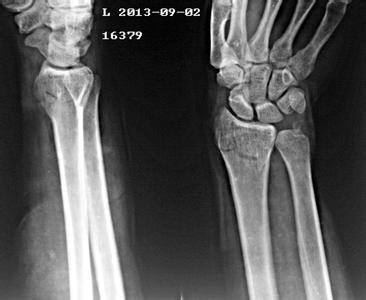

骨折后要如何预防骨不连的发生?

骨折后要预防骨不连的发生:骨不连,就是指骨折不愈合。云南骨科医院专家介绍,骨不连是骨折不愈合的现象,有自身原因,也有外界影响,都可能发生,引起发生骨折部位不愈合之后的治疗很困难,所以要尽量避免骨不连的发生。